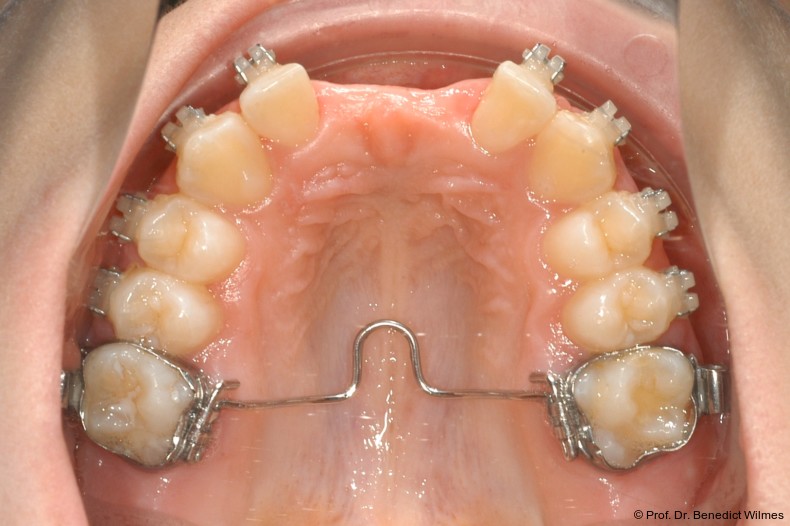

Ein 14-jähriger Patient wurde bei Aplasie der beiden oberen seitlichen Schneidezähne mit dem Ziel der beidseitigen Lückenöffnung kieferorthopädisch therapiert (Abb. 1a+b). Zum Ende der kieferorthopädischen Behandlung wurden zwei Miniimplantate in Regio 2er als temporärer Zahnersatz inseriert (Benefit System, PSM, 2 x 13 mm, Abb. 2a+b). Nach Abdrucknahme wurden Kronen auf den Peek-Abutments modelliert und diese mit Kunststoff auf die Abutments geklebt (Abb. 3a–d). In den Abbildungen 3 und 4 sind die klinischen und röntgenologischen Nachkontrollen innerhalb der nächsten achteinhalb Jahre dokumentiert. Man erkennt einen sowohl in der Höhe als auch in bukkopalatinalen Breite verbleibenden gesunden Knochen ohne Anzeichen einer Atrophie. Im Alter von 23 Jahren wurden die definitiven Implantate ohne die Notwendigkeit einer Augmentation eingesetzt (Abb. 5) und nach Einheilung prothetisch versorgt (Abb. 6a–e und Abb. 7a–c).

Nach Abschluss der kieferorthopädischen Pfeilerverteilung wurden zwei Miniimplantate in Regio 3er inseriert (2 x 13 mm). Nach Herstellung im Labor wurden Kronen auf den Miniimplantaten aufgeschraubt (Abb. 13+16a–d). Auch hier wurde darauf geachtet, dass die Kronen aus der Okklusion geschliffen wurden (Abb. 14). Bei den Nachkontrollen zeigten sich ebenfalls stabile Miniimplantate und ein entzündungsfreies Implantatlager ohne erkennbare Atrophie des Knochens (Abb. 15 und 16a–d).